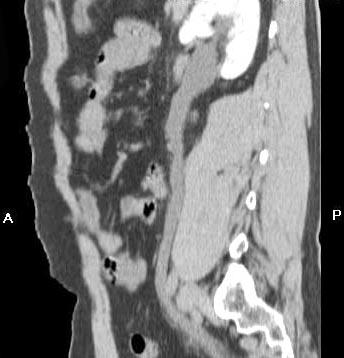

问题 男,29岁,下腹部疼痛不适伴血尿2 月,CT检查如图,下列说法错误的是 ( )

选项 A、考虑为盆腔静脉石 B、考虑为左输尿管下端结石 C、左侧输尿管扩张 D、左肾积水 E、左侧输尿管末端膀胱入口处可见一高密度影

答案 A